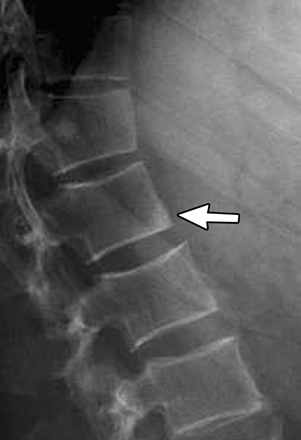

Kummel disease

Kummel disease is the eponym for avascular necrosis of the vertebral body after a vertebral compression fracture

Vertebral body contains air

Note: normally, anterior margin of the vertebral body should be concave! Note the image below!